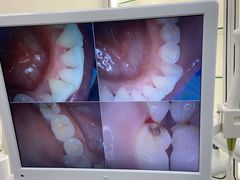

• 牙博士口腔品牌连锁(杨浦店)

• -牙博士口腔品牌连锁(杨浦店)